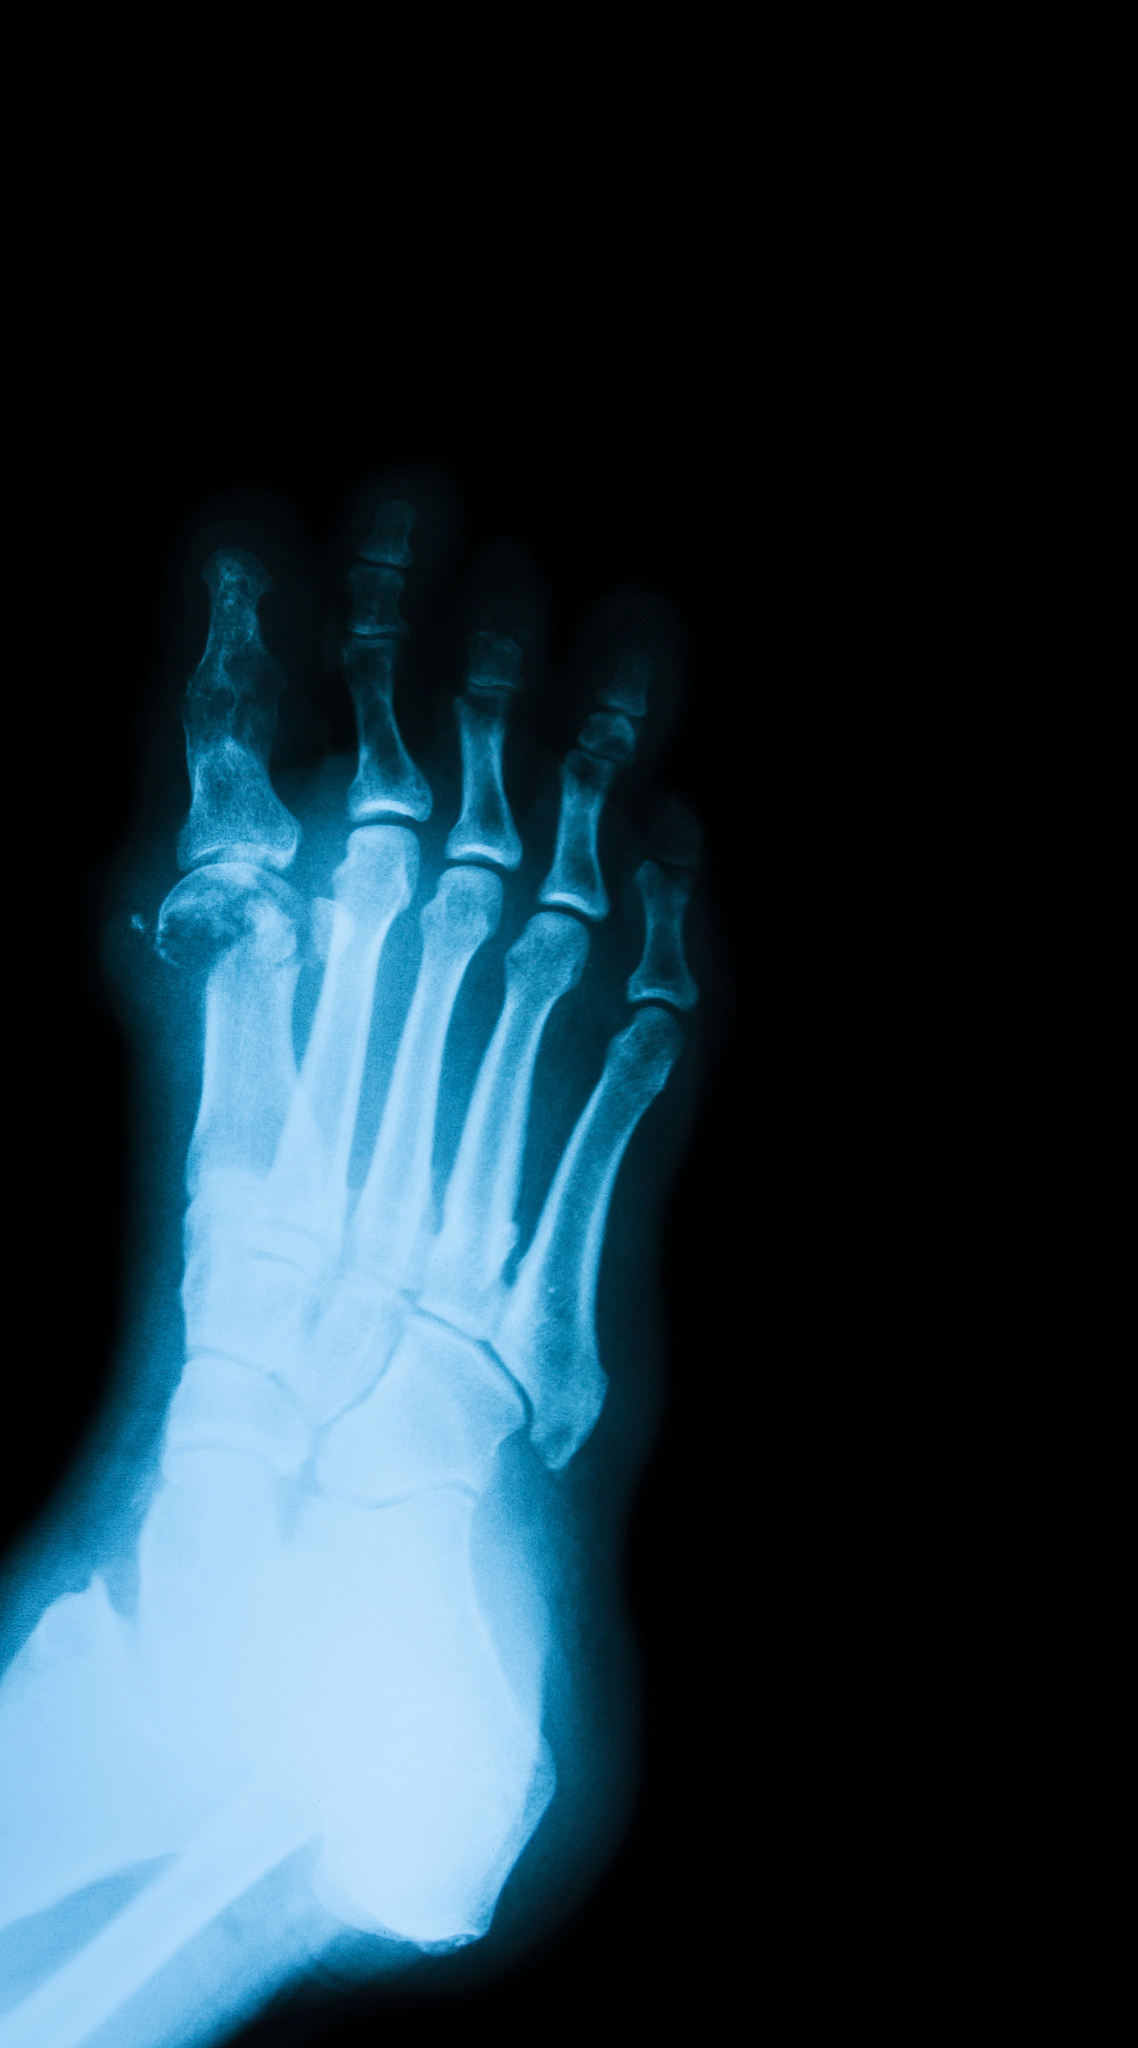

3. 糖尿病足坏疽:由于糖尿病引起的微循环障碍和感染导致组织缺血坏死,常见于足部。

常见的坏疽部位包括四肢末端、足部、肛门、会阴、乳房、口腔等。